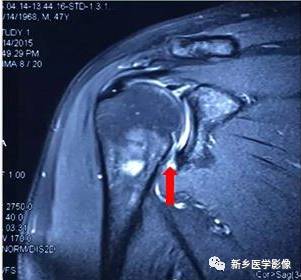

病例五:

红色箭头:巨大肩袖损伤(冈上肌腱回缩至关节盂后方)